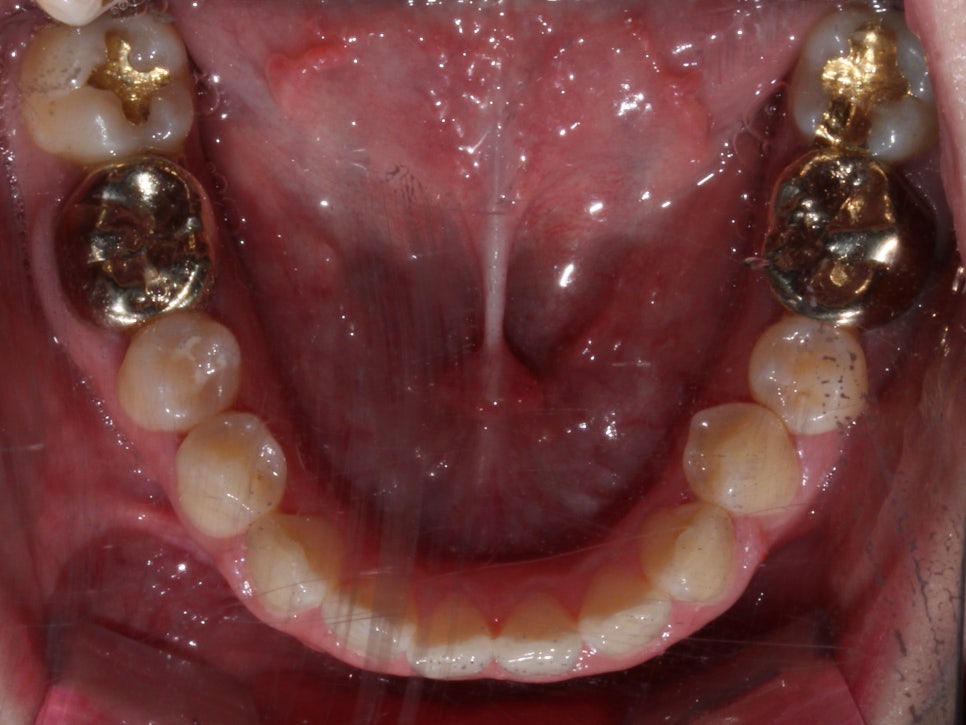

첫 방문

처음 방문 하셨을 때 모습입니다.

오른쪽 두번째 앞니가 거꾸로 물리는 상태이고

(사진상 왼쪽)

윗니가 전체적으로 삐뚤빼뚤한 것이 보입니다.

잘 보이실진 모르겠지만,

우측 구치부는 전반적으로

거꾸로 물리는 양상이 보입니다.

왜 이렇게 물리는가 ? 보면

아래턱 자체가 오른쪽으로 돌아가있는

골격적 구조를 가지고 있습니다.

위 중심선은 괜찮지만

아래 중심선이 우측으로 치우쳐 있고

(사진상 왼쪽으로)

그러다보니 당연히

오른쪽은 조금더 반대로 물리는 성향을

띄게 되겠죠?

골격적 비대칭으로 인해 좌우 높이도

많이 달라보입니다.